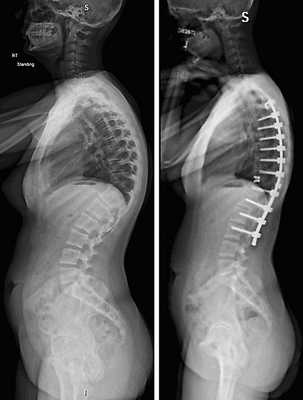

Стабилизация поясничного отдела.

Показаниями к вживлению ригидных конструкций транспедикулярной фиксации, в том числе и Krypton®, служат практически все случаи позвоночной нестабильности:

- выраженный листез позвонков;

- травмы позвоночника (вывихи, переломы и пр.);

- спинальные новообразования;

- дегенеративные патологии, сопровождающиеся неврологическим дефицитом, например, межпозвоночные поясничные грыжи; и кифоз;

- несостоявшийся артродез;

- последствия неудачно выполненных вмешательств и др.

Коррекция кифоза грудного отдела.